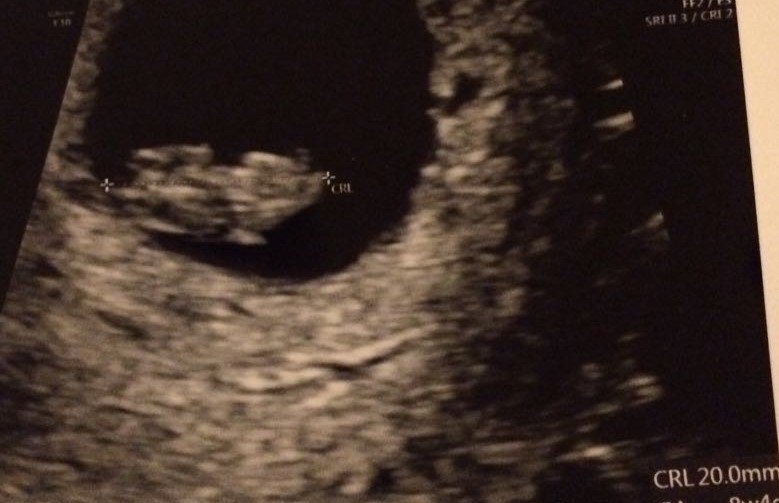

8+5 weeks

Attachment 28530